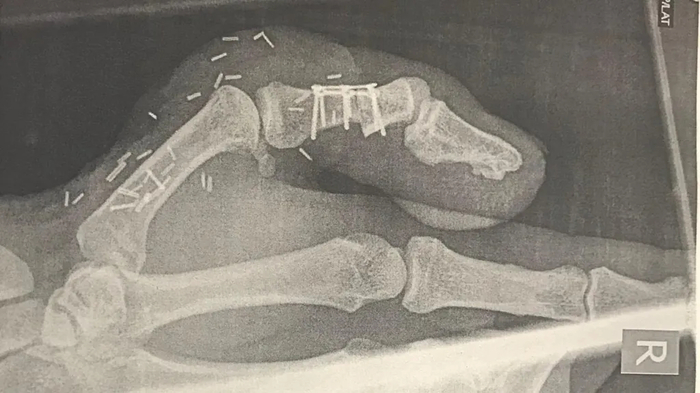

두 번째 선택지는 엄지발가락을 떼어내 엄지손가락에 붙이는 방법이었다. 리는 이 방법을 선택해 엄지손가락의 빈자리를 엄지발가락으로 메웠다.